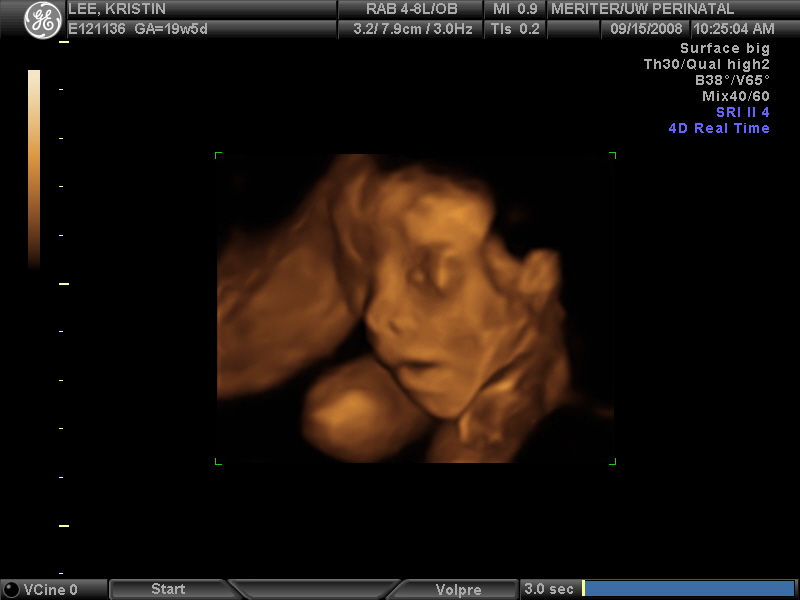

Ultrasound